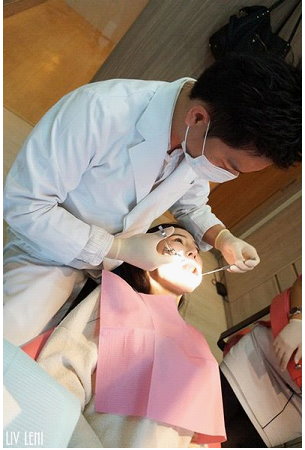

2015.01.09 最終成績檢查

(圖中醫師正拿著牙周探測器,測量我的牙周囊袋。)

很外的就來到最後一個環節啦~~

這個步驟是醫師拿牙周探測器,

測量經過刮除治療與正確刷牙後,牙周囊袋有無改善。

結 果 出 來 了 !

前排牙齒變得更健康了,從原本的3釐米,變成2釐米,

後面囊袋4、5、7、8釐米的深度,都恢復成3釐米了!!

真是太不可思議了!

也好開心~好感動~~~努力好有收穫呢!!!